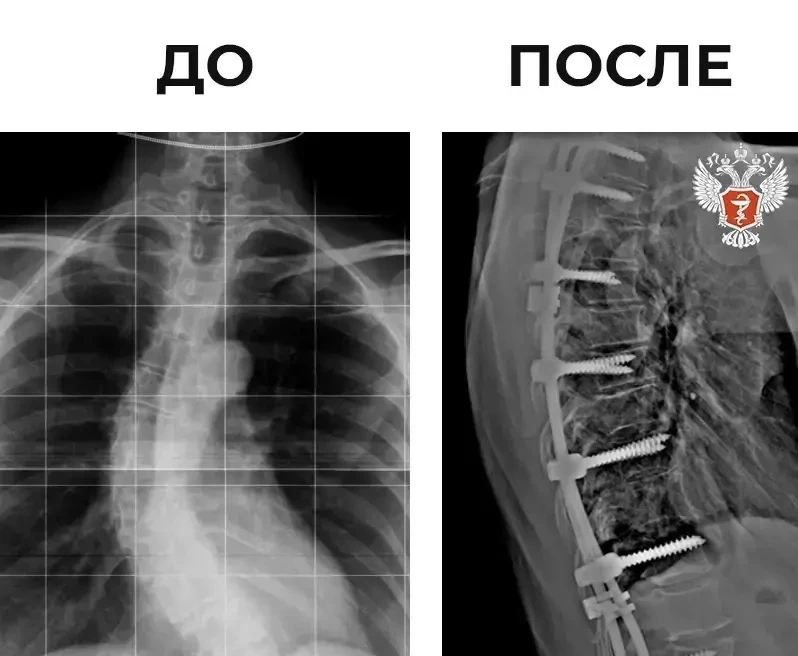

🧍‍♂ Михаил Мурашко: Ортопедия — одно из направлений медицины, которое позволяет человеку чувствовать себя активным и получать удовольствие от жизни

Об этом заявил министр здравоохранения РФ Михаил Мурашко в ходе выступления на XII Всероссийском Приоровском форуме, посвященный 140-летию со дня рождения НМИЦ травматологии и ортопедии им. Н. Н. Приорова Минздрава России.

— Ортопедия является, по сути, одним из основополагающих направлений, наряду с когнитивным здоровьем. Именно эти два момента позволяют человеку чувствовать себя активным, полноценным гражданином и получать от жизни удовольствие, — рассказал он.

➡️ Михаил Мурашко подчеркнул стратегическую роль ортопедии в рамках национальных проектов, направленных на увеличение продолжительности здоровой жизни.

Также министр отметил положительные тенденции в отрасли ортопедии:

➡️ Увеличение объема оказываемой помощи;

➡️ Расширение технологий с использованием роботизированных методов;

➡️ Повышается качество эндопротезов.

— Хочу отметить, что НМИЦ травматологии и ортопедии им. Н. Н. Приорова Минздрава России всегда были приверженцами и последователями системы менеджмента качества, позволяющие расширять и внедрять новые технологии, обеспечивая их безопасность для пациента, — рассказал он.

Особое внимание Михаил Мурашко уделил роли благотворительного фонда «Круг добра» в финансировании высокотехнологичной помощи, в том числе уникальных операций для детей.

— Все эти возможности появились благодаря тому, что фонд «Круг добра» слышит нас. Для развития ортопедии у нас сегодня есть и материально-технические базы, и источники финансирования, — отметил он.